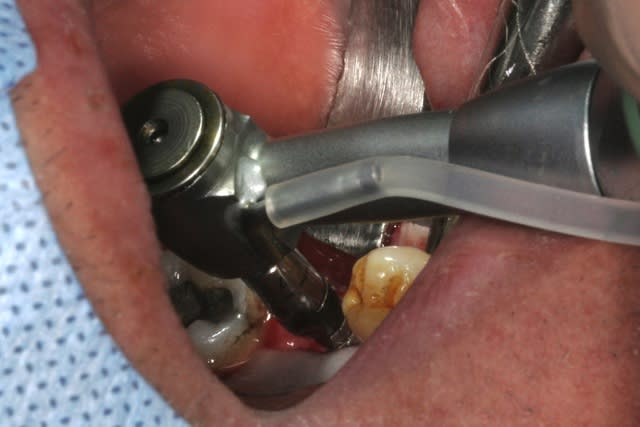

forage, tout ce qu'il y a de plus classique pour ceux qui connaissent ID ou zimmer

pour un implant de 5mm de diamètre on s'arrête au foret de 4.4, passé ici sur 8mm au lieu des 11.5mm car j'étais dans du D3